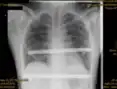

Pectus excavatum on PA chest radiograph with shift of heart shadow to the left and radioopacity of the right paracardiac lung field

Chest x-rays are also useful in the diagnosis. The chest x-ray in pectus excavatum can show an opacity in the right lung area that can be mistaken for an infiltrate (such as that seen with pneumonia).[20] Some studies also suggest that the Haller index can be calculated based on chest x-ray as opposed to CT scanning in individuals who have no limitation in their function.[21]